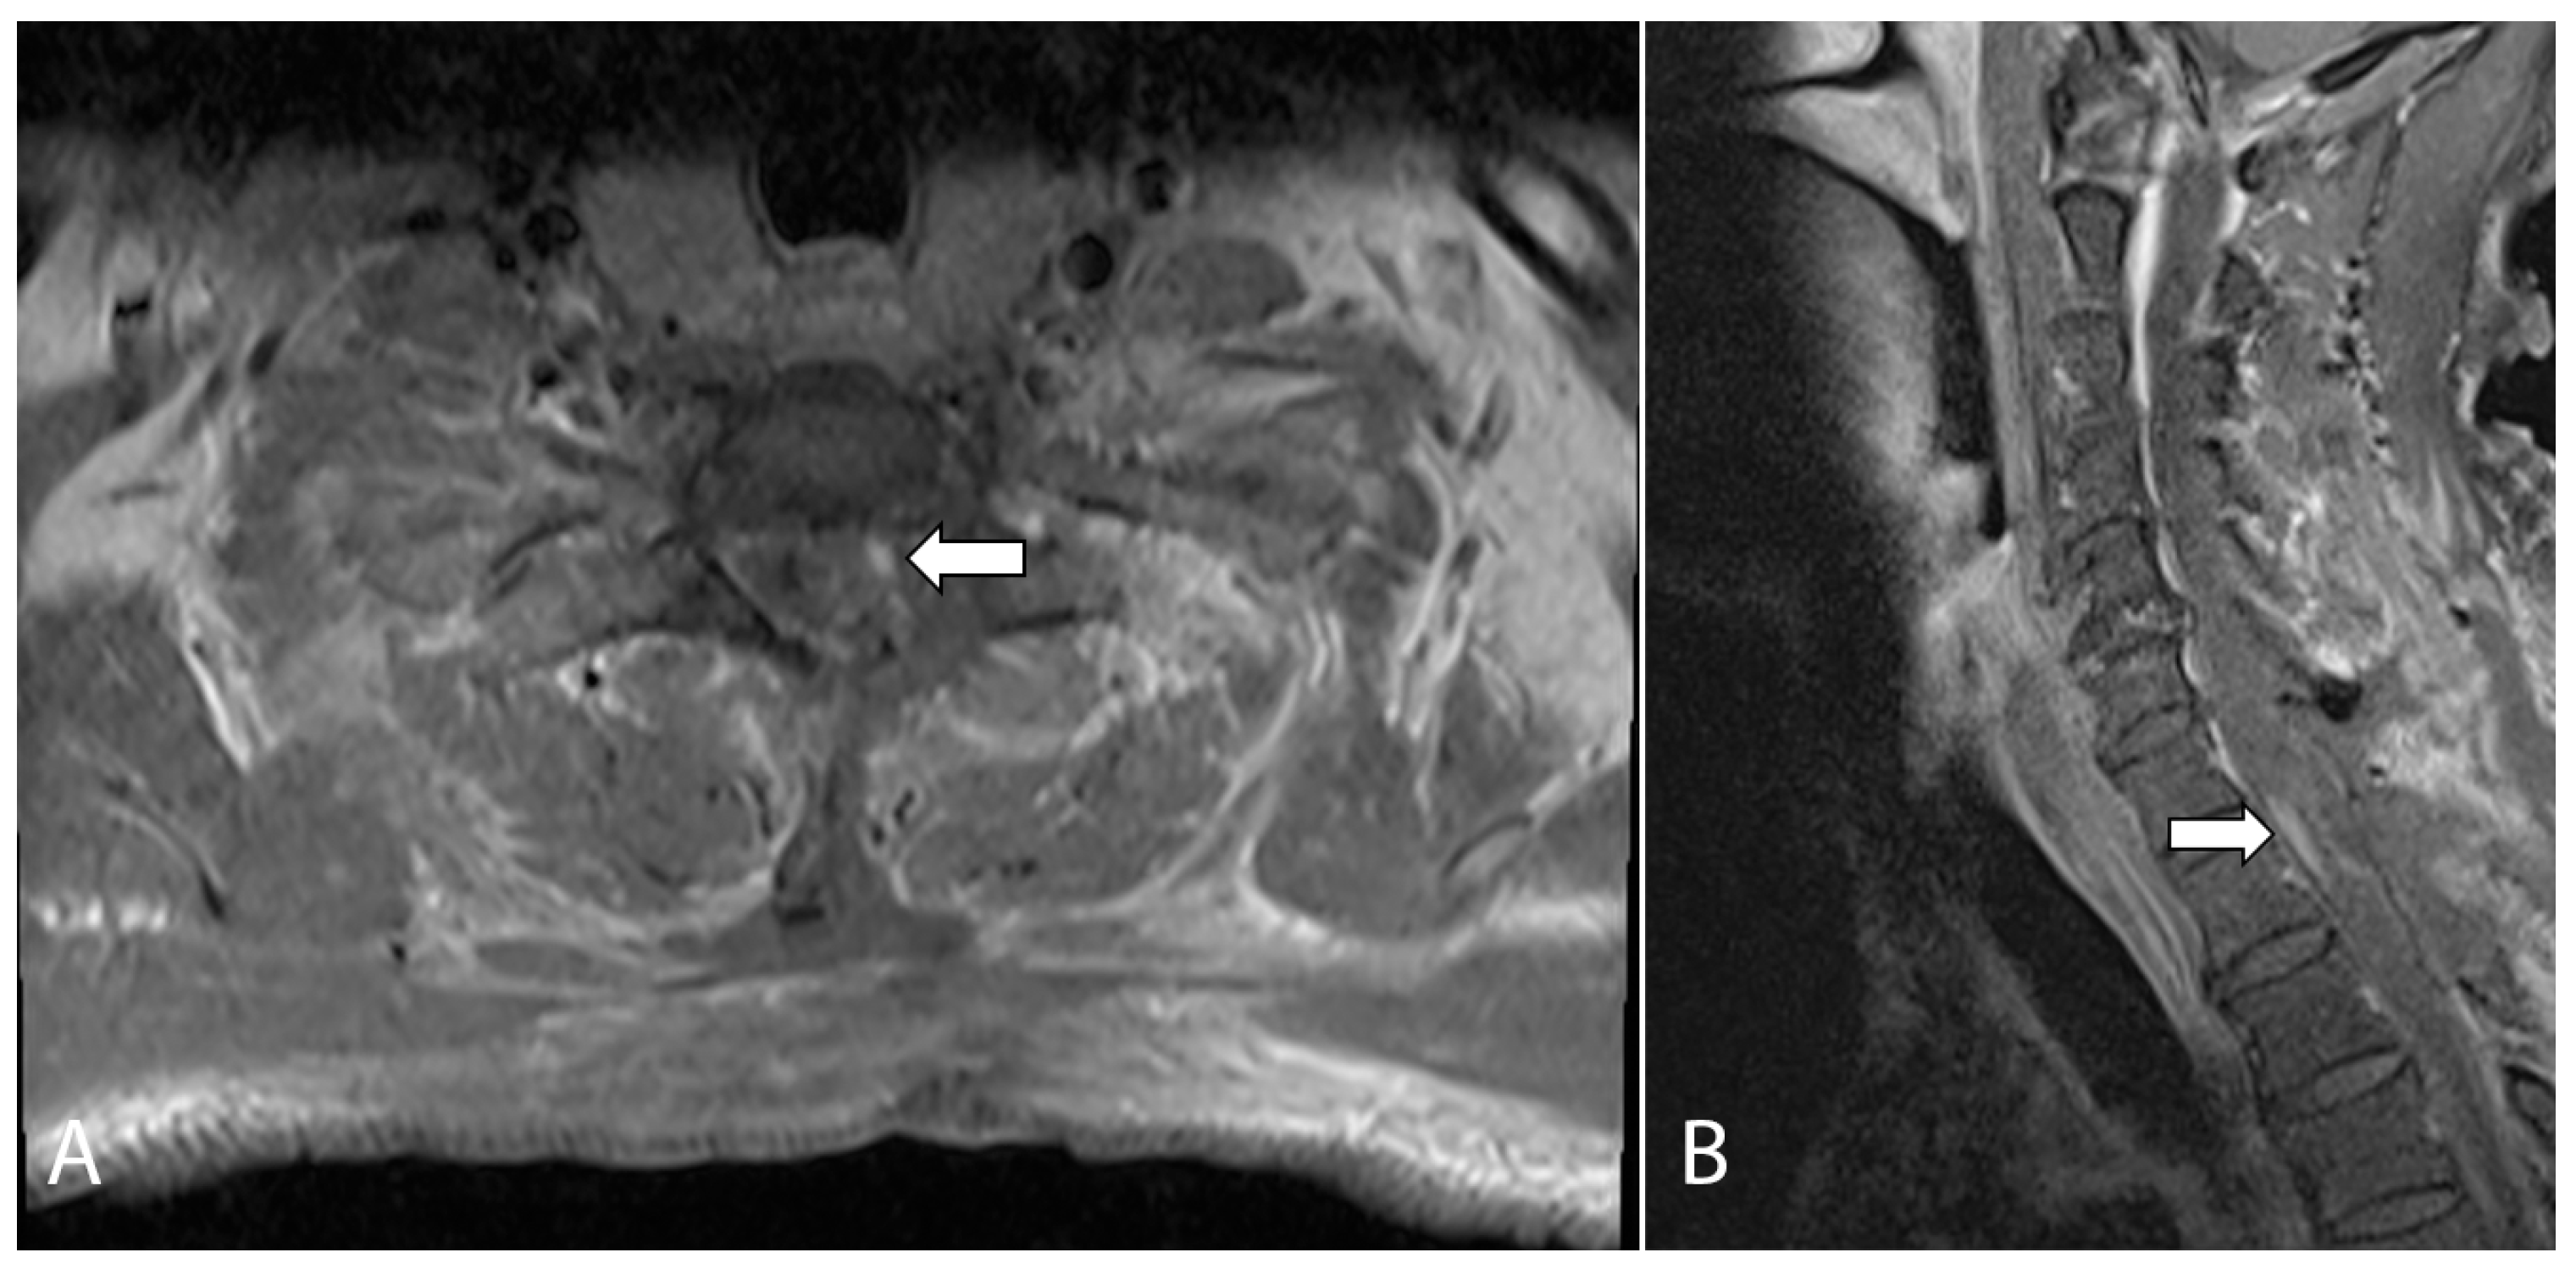

Magnetic resonance imaging (MRI) of his cervicothoracic spine and left brachial plexus demonstrated a 1.3 × 0.7 × 0.8 cm intraspinal mass centered at the level of T1 on the left. This lesion was heterogeneous and infiltrative, with poorly defined margins. It had an iso- to hypointense T2-weighted signal and demonstrated heterogeneous contrast enhancement. It appeared predominantly intramedullary in location with associated expansion and edema of the spinal cord. However, there was also thickening and enhancement along the left T1 nerve root with expansion of the left neural foramina, as well as a nodular enhancing focus which appeared extramedullary in location (Figure 1). On the basis of these initial clinical and imaging findings, the working diagnosis was that of an infective or inflammatory process resulting in leptomeningeal and perineural disease, with the differential diagnosis including secondary metastatic deposits or an underlying primary central nervous malignancy. However, an MRI brain study, as well as computed tomography of the thorax, abdomen, and pelvis, was unremarkable, with no other masses or metastatic disease elsewhere. Lumbar puncture was performed, and cerebrospinal fluid analysis did not yield any positive microbiological culture, viral DNA PCR results, or any malignant cells.

Figure 1.

(A) Initial sagittal T2-weighted MRI of the cervical spine showed long segment cord signal change/edema and cord expansion. (B) Axial T1-weighted, fat-suppressed, contrast-enhanced MRI of the cervical spine shows an enhancing intramedullary lesion at the level of T1 (short arrow). There is also a nodular enhancing focus which appeared extramedullary in location (long arrow). (C) Axial T1-weighted, fat-suppressed, contrast-enhanced MRI of the brachial plexus at a level slightly inferior to (B) shows abnormal thickening and enhancement along the left T1 nerve root (arrow), suspicious for perineural disease spread.